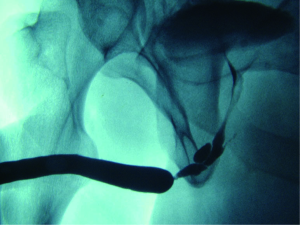

Given that retrograde urethrogram relies on an intraluminal opacification of the urethra, it provides minimal direct assessment of periurethral pathology. Retrograde urethrogram is limited in its assessment of spongiofibrosis, which can be interpolated through the examiners diagnostic suspicion and experience. In most situations, however, complicating features such as fistula, false passage, and significant ductal reflux can be readily identified (10) (Figure 5).

In the setting of traumatic urethral disruption, retrograde urethrogram plays a central role. Not only is it indicated in acute diagnosis and assessment of these injuries, it carries a central role in operative planning for reconstruction of these defects. The degree of urethral distraction and measurement of bulbar length, or urethrometry, can be easily performed with this study (11). Such measurements are critical to planning operative approaches for repair of these injuries (12). Severe urethral occlusion may lead to inadequate visualization, which can require combination antegrade urethrography in order to fully delineate the stenosis (13).